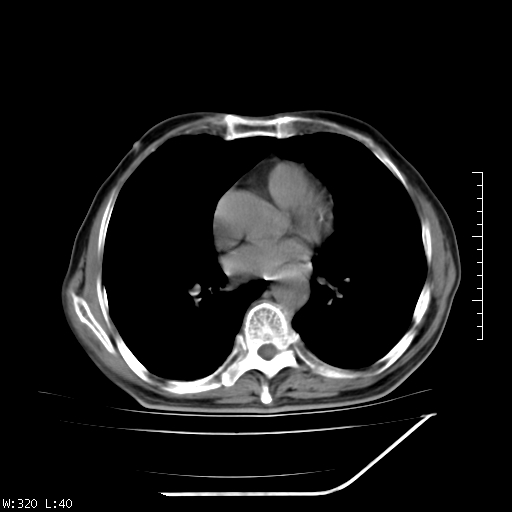

标题: CT23994:男、72、咳嗽、气短两月余,近来消瘦。 [打印本页]

标题: CT23994:男、72、咳嗽、气短两月余,近来消瘦。

右上肺实变,与胸膜关系密切,右肺容积缩小,隆突下淋巴结增大,考虑1 肺结核 2 肺癌

右上肺大片状密度增高影,与胸膜关系密切,内见低密度透亮影,胸膜下可见三角形不张影,左下肺沿支气管走形结节影,纵膈内淋巴结显示。考虑结核并疤痕性不张可能性大,建议穿刺活检,排除肺泡癌。